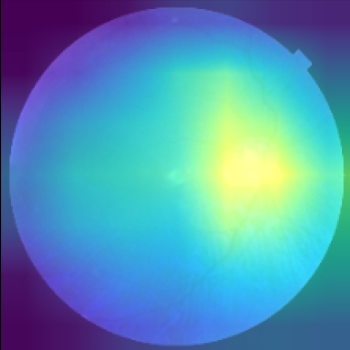

Class activation heat-map development

The final step involves the generation of feature visualisation heat-maps, elucidating the decision-making process of the trained model, and assessing its reliability. Feature visualisation is valuable for uncovering and understanding the learnt features within DL models. Zhou et al. (2016) introduced the Class Activation Mapping (CAM) method, which incorporates a global average pooling layer into a standard CNN. This innovation facilitated the identification of critical feature contributions linked to CNN’s specific predictions, shedding light on the rationale behind the model’s decisions. Furthermore, Selvaraju et al. (2017) introduced Gradient Weighted Class Activation Mapping (Grad-CAM), using gradients from the network’s final convolutional layer to generate a coarse localisation map. This map highlights influential regions within an image that contribute to the prediction of specific concepts or classes. In our study, we embraced the Grad-CAM technique on the model’s final layer to generate class-specific heat-maps. The objective is to unveil evidence of how the models arrive at predictions, with the heat-maps delineating regions of significance in the model’s prediction rationale.

Comparison using XAI techniques